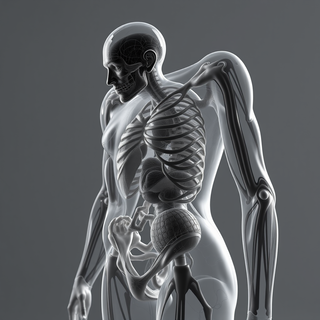

Creates ultra-detailed, multi-layer 3D anatomical visualizations from reference photos.Open

Creates ultra-detailed, multi-layer 3D anatomical visualizations from reference photos.Open

Transform photos into scientific anatomical illustrations.Open

Transform photos into scientific anatomical illustrations.Open